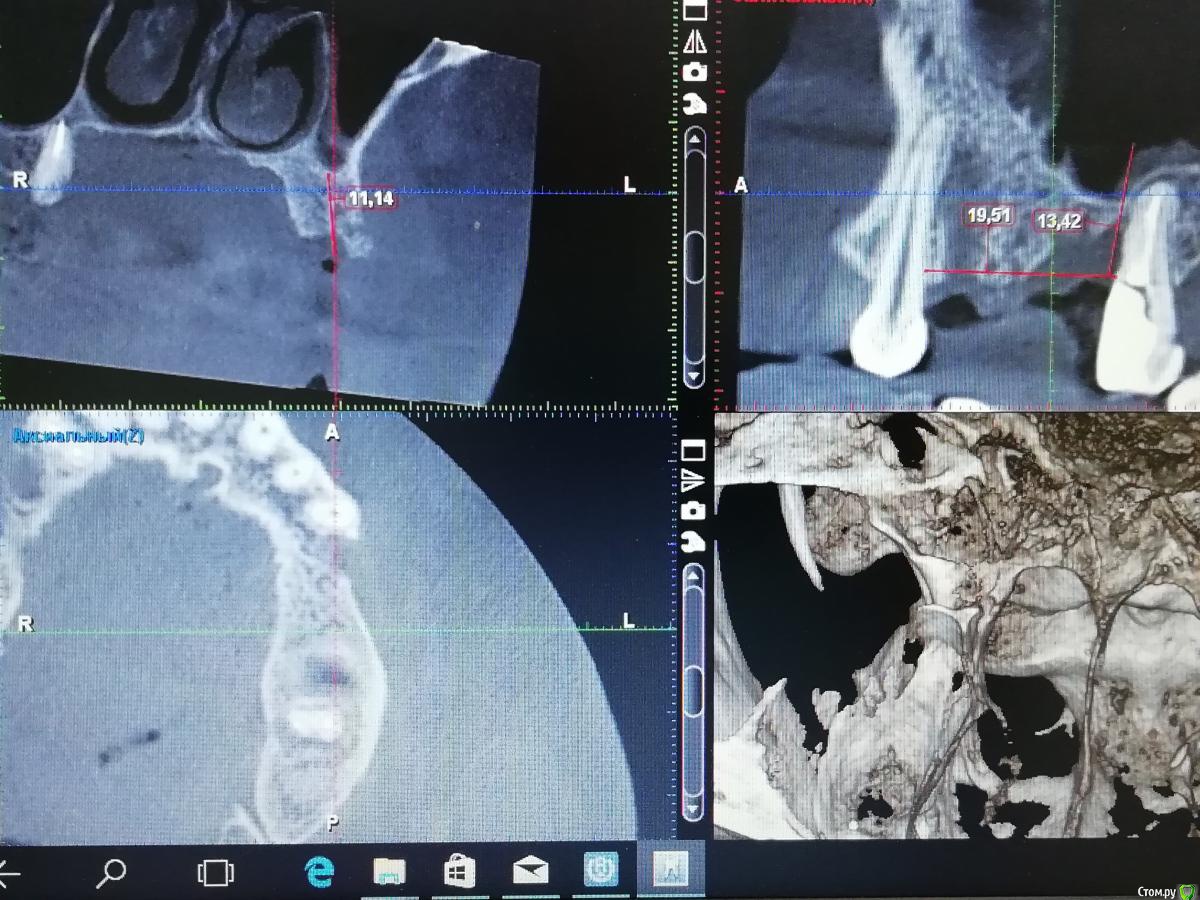

___49___ Опубликовано 23 декабря, 2019 Поделиться Опубликовано 23 декабря, 2019 (изменено) 6 месяцев назад , проведено РВК двух корней 14 зуба с ретроградкой триоксидентом, в дефект заложена гемостатическая губка на линкомицине, в месте доступа подсыпан чистый ксено с излишком . Синуслифтинг в области 16 и 15 го отсутствующих зубов , Ксено +ауто и под них 3 губки на линкомицине (участок с молодыми костными балками без ксено на фото - между графтом и старой границей кости ) . Область окна при синусе и немного вестибулярнее смесь ксено + ауто с излишком ( как говорил учитель если есть ширина то будет и высота , в том числе и как опора для мягкотканной пластики если понадобится ) . все перекрыто резорбируемой мембранной на пинах. Азитромицин перед операцией . Изменено 23 декабря, 2019 пользователем ___49___ 1 Ссылка на комментарий

___49___ Опубликовано 23 декабря, 2019 Автор Поделиться Опубликовано 23 декабря, 2019 НКР вестибулярно в области 24 зуба ксено +ауто, НКР вертикально в области 26го зуба ксено +ауто(утрамбовано очень плотно) , Синуслифт в области 26 и 25 го ксено +ауто, из чистого ксено сделана боковая поддержка вестибулярно для будущих мягких тканей в области 26 и 25 , все перекрыто резорбируемой мембраной на пинах.. Через 4.5 месяца удален 27 ой зуб , заложена губка плотно ( уже появляются первые балочки на Rg). 1 Ссылка на комментарий

___49___ Опубликовано 23 декабря, 2019 Автор Поделиться Опубликовано 23 декабря, 2019 Планирую Импланты:обл16 - 6х8 обл 24- 4.5х12обл 26- 6х12 Коментарии, критика , свое виденье планирования уважаемые коллеги высказывайте. Спасибо . Ссылка на комментарий

Дмитрий М Опубликовано 7 января, 2020 Поделиться Опубликовано 7 января, 2020 На срезе в первом секторе материал "висит" над костью в пазухе. Что-то нерентгенконтрастное? Во вотором секторе лунка удаленного зуба выглядит пустой. Метериал не вносили?сначала тоже так подумал, но это губка! как я понял ильгамовская)): Ксено +ауто и под них 3 губки на линкомицине (участок с молодыми костными балками без ксено на фото - между графтом и старой границей кости ) 1 Ссылка на комментарий

___49___ Опубликовано 7 января, 2020 Автор Поделиться Опубликовано 7 января, 2020 (изменено) Во вотором секторе лунка удаленного зуба выглядит пустой. Метериал не вносили? Во втором секторе , 27 зуб был удален полсе НКР через 4.5 месяца, лунка (благодаря НКР) теперь имеет все 4 стенки , так как графт был в контакте с зубом 27 (который временно выполнял роль дополнительной стенки) он мог быть обсеменен, свободно лежащие частички графта я убрал и заложил губку на линкомицине - так же максимально желая предотвратить возможное инфицирование графта , но при этом сильно не потерять в кости - чего и добился - фото с расставленными имплантами через 1-2 месяца после удаления 27 го. Что касается губки - она очень хорошо прорастает молодыми сосудами , что играет большое значение в трофике оставшейся кости,а также новой (ксено +ауто) - это сугубо мой личный вывод(не факт что верный) Изменено 7 января, 2020 пользователем ___49___ Ссылка на комментарий